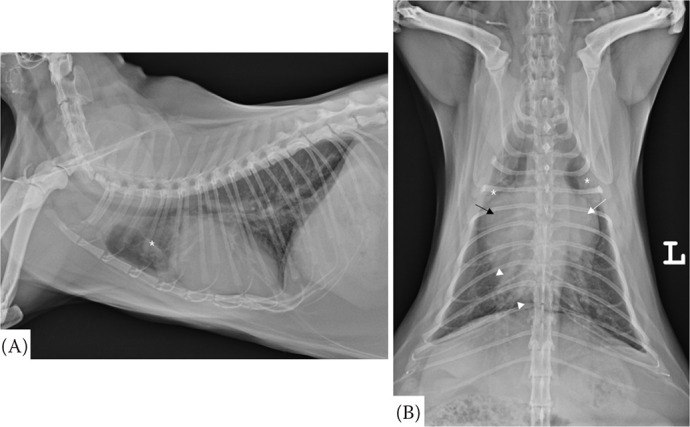

一只6岁的雌性绝育土耳其安哥拉猫因呼吸急促而被转诊。该患者两年前在当地医院进行健康检查时被诊断为心脏肥大。呼吸急促发生在一年前。体格检查时,患者呼吸频率为每分钟72次,收缩压为70 mmHg。胸片显示严重的心脏肥大,左心房(LA)增大,右心房(RA)增大,右心室增大,肺动脉和肺静脉扩张。在右、左颅肺叶可见肺泡型。超声心动图显示一层膜将左心室分为两个腔室,下房间隔缺损,前或后三尖瓣(TV)伸长。然而,没有观察到间隔电视。在心脏收缩期,经房间隔缺损证实血流量从左心房流向右心房。舒张期,血流量从左室到左室被证实。这些结果提示心房三房性心绞痛(CTS)合并部分房室间隔缺损(AVSD)。本报告描述了超声心动图诊断CTS合并部分AVSD的猫。

A 6-year-old female neutered Turkish Angora cat was referred due to tachypnoea. The patient was diagnosed with cardiomegaly at a local hospital during a health screening two years ago. Tachypnoea occurred one year ago. On physical examination, the patient presented with a respiratory rate of 72 breaths per minute and a systolic blood pressure of 70 mmHg. Thoracic radiographs revealed severe cardiomegaly, left atrium (LA) enlargement, right atrium (RA) enlargement, right ventricular enlargement, and dilation of pulmonary arteries and veins. An alveolar pattern was identified in the right and left cranial lung lobes. Echocardiography revealed a membrane that divided the LA into two chambers, a defect in the lower atrial septum, and elongation of anterior or posterior tricuspid valves (TV). However, septal TV was not observed. During systole, blood flow from LA to RA was confirmed through a defect in the atrial septum. During diastole, blood flow from LA to left ventricular was confirmed. These findings suggest cor triatriatum sinister (CTS) with partial atrioventricular septal defect (AVSD). This report describes echocardiographic diagnosis of CTS with partial AVSD in a cat.